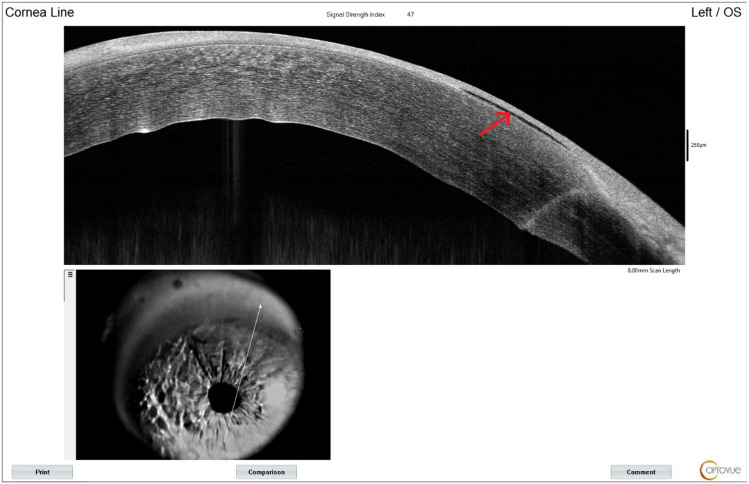

Case presentation: A 63-year-old male developed bilateral DME following cataract surgery with intraocular lens implantation. His best-corrected visual acuity (BCVA) was 0.15 in the right eye and 0.5 in the left eye. The patient underwent bilateral intravitreal injections of the anti-VEGF agent conbercept. During preparation for the injection in the left eye, corneal epithelial bleb formation was observed. The patient received corneal patching therapy, with complete epithelial healing observed by day 10 post-injection. This case underscores the need for vigilant corneal monitoring during and after intravitreal injections in diabetic patients with prior cataract surgery.